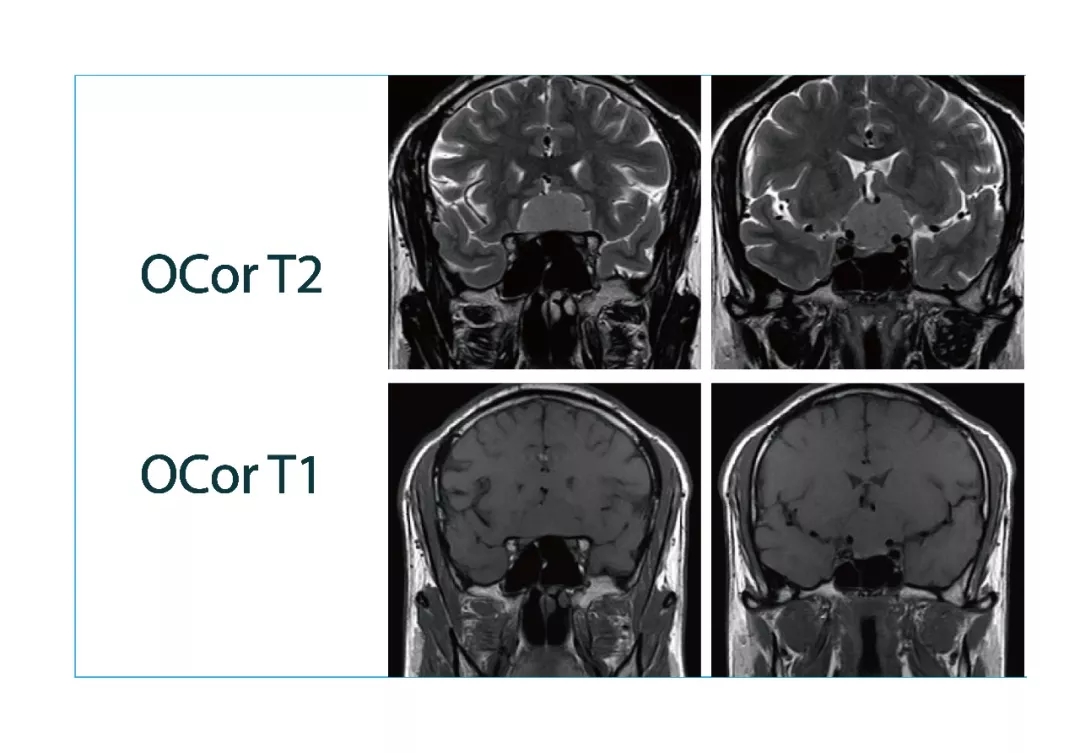

【朗润影像档案】磁共振影像病例分享(编号20180105)